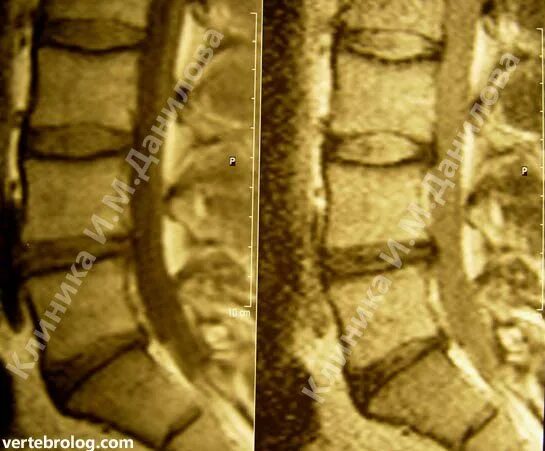

Операция грыжа l5 s1